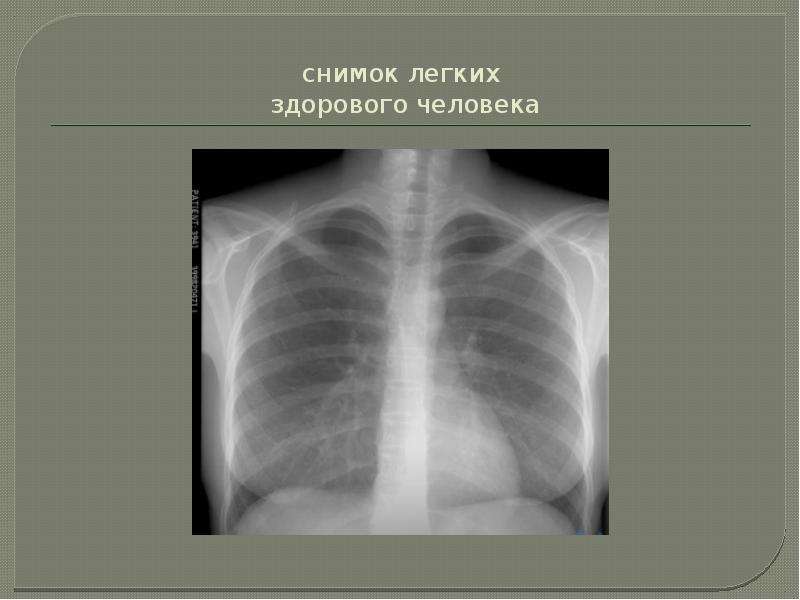

Снимок грудной клетки здорового ребенка: примеры и диагностика

Раздел: Мудрость в объективе